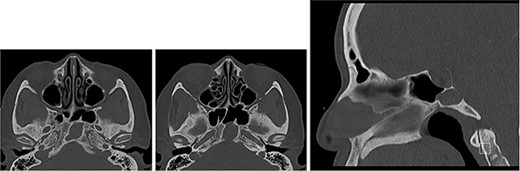

CT of the base of skull (axial images ×2 and sagittal image) showing sphenoid mucocele and paper-thin posterior cortex.

A CT head following her acute presentation showed no intracranial event (Fig. 4). There was minimal change in the size of the mucocele. Both anterior and posterior clival dehiscence had increased, reflecting remodelling or pressure deossification. The dehiscence was contiguous with a new smooth plaque of dural retroclival thickening that extended from the petrous ridge/dorsum sellae cranially to the basion caudally, features that are non-specific for extruded proteinaceous mucocele.

CT of the head (left: sagittal bone and soft tissue windows, and, right: axial bone window and soft tissue window at the same levels ×2) showing sphenoid mucopyocele, retroclival dural thickening and increasing clival dehiscence (anterior and posterior cortex).